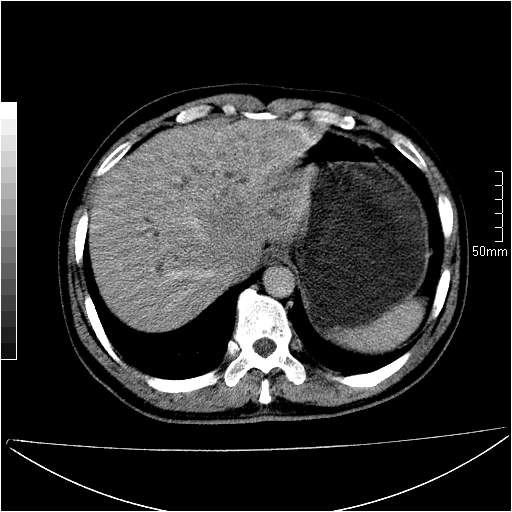

男性,54岁,皮肤黄染,搔痒一周余.b超示肝左叶回声异常.初步诊断1胆总管下段结石2胆囊结石伴慢性胆囊炎请各位战友帮忙看一下肝脏多发低密度如何解释恰当.增强效果不是很好.请大家见谅.

胆总管及肝内胆管扩张,考虑是结石!但,肝内的低密度区增强不明,可能是肝ca,因为肝ca在增强时呈快进快出.另年胆总管扩张原因,可以考虑一下是不是,胆管ca.再次要考虑肝内的低密度是否为海绵状血管瘤所致!

首先,胆总管下端结石梗阻伴肝内胆管扩张可确定。

其次,增强动脉期肝静脉显影,肝实质密度不均。——此为右心功能不全引起肝淤血的表现。

另外,肝八段低密度占位,呈多灶性,考虑肝脓肿或肝癌可能,(图像质量欠佳)建议进一步检查。